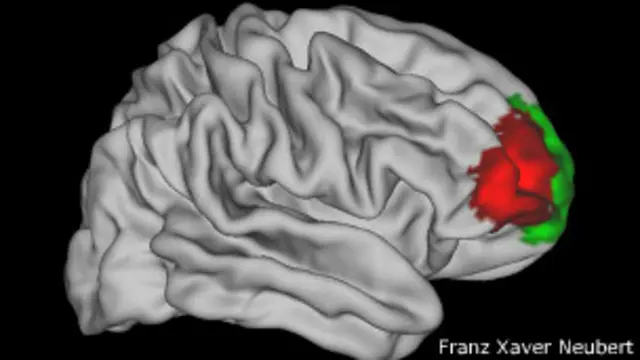

En su trabajo, los científicos identificaron y analizaron 12 subregiones de la parte frontal del cerebro y sus patrones de conectividad con otras zonas, que identificaron como huellas.

Luego las buscaron en el cerebro de mono, y así encontraron las similitudes que se ven, marcadas con colores, en la imagen de más arriba. El cerebro del extremo izquierdo es humano, el de abajo es de mono.

De las 12 subregiones, 11 eran muy similares en las dos especies.